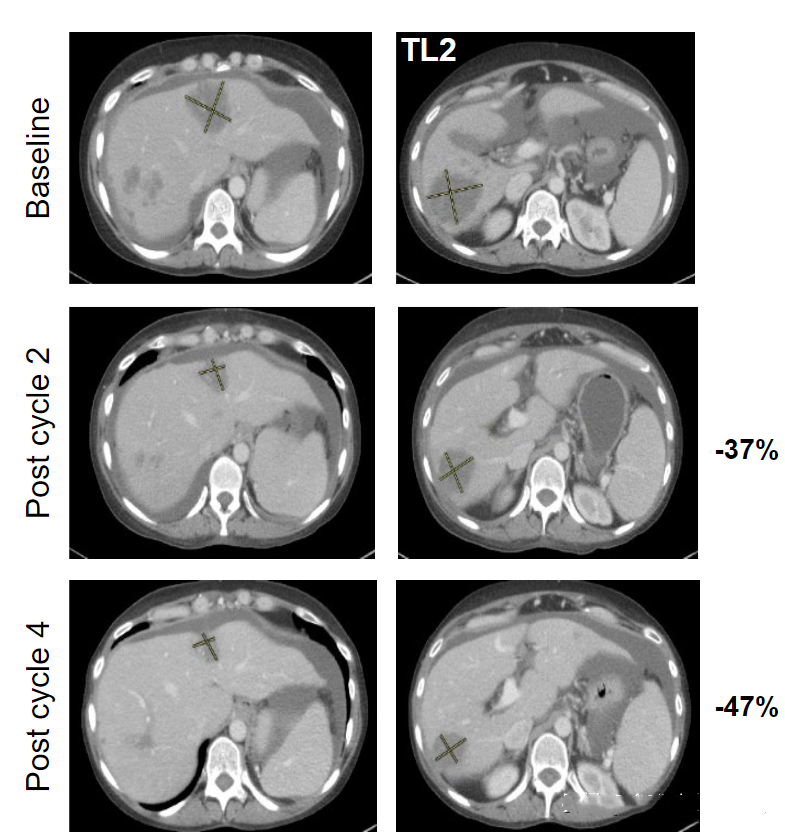

在王阿姨接受新药2周后肿瘤病灶开始出现了缓解,肿瘤缩小近37%。3周的新药治疗过后,肿瘤病灶缩小47%,同时临床症状也有明显好转。在该试验数据发表时,王阿姨仍还在接受该方法治疗中。

治疗后的检查